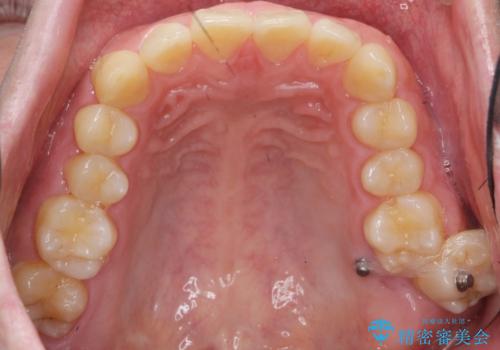

左上の奥歯がシザーバイトがありました。

部分矯正を行いシザーバイトを改善した後、インビザラインで歯列を整えました。

歯のがたつきが改善され大変お喜びいただけました。